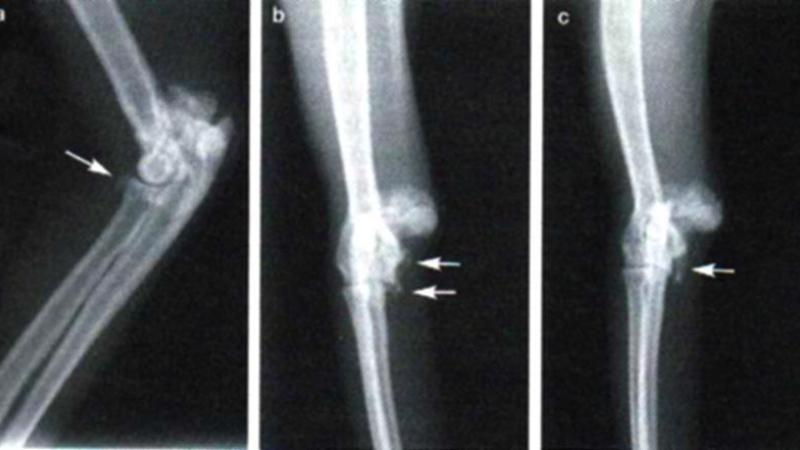

Наиболее часто встречается остеоидная остеома большеберцовой кости. Реже наблюдаются остеомы бедренной, малоберцовой, плечевой, лучевой и плоских костей.

- Болевые ощущения в области пораженной кости. Сначала они напоминают мышечные боли, но со временем усиливаются. Боль возникает при начале движения, затем может уменьшаться или исчезать, но в состоянии покоя возвращается.

- Образование болезненного инфильтрата над пораженной областью, который развивается со временем. Это скопление клеток с добавлением лимфы и крови.

- Если остеома находится на ноге, может возникнуть хромота.

- При локализации вблизи зоны роста кости у детей может наблюдаться асимметрия скелета.